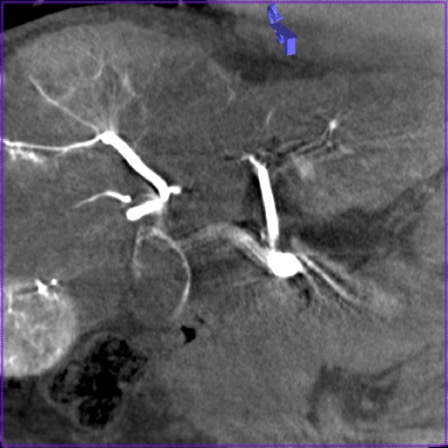

Высокое пространственное разрешение является ключевой сильной стороной ПДКТ, благодаря которой достигается четкая визуализация сосудов диаметром 250–300 мкм (0,25-0,30 мм) при проведении ПДКТ-артериографии (рис. 1). Такое высокое разрешение ПДКТ позволяет осуществлять прецизионный 3D-контроль установки стентов, микрокатетеров, тонких пункционных игл и других устройств непосредственно в рентгеноперационной (рис. 2). Пространственное разрешение характеризует точность воспроизведения малых структур в изоцентре и зависит от ряда факторов, таких как шаг пикселя, площадь сцинтиллятора, размер фокального пятна, геометрическое увеличение, стабильность системы во время сканирования, а также используемых фильтров реконструкции. Как уже было отмечено, применяемые в настоящее время a-Si:H/CsI:Tl ПДКТ-детекторы имеют высокие частотно-контрастные характеристики, благодаря конусовидному направлению света к каждому фотодиоду. Более толстый слой CsI улучшает поглощение, но увеличивает боковое размытие, снижающее контрастность, поэтому толщина и размер пикселя оптимизируются совместно [3, 4]. Пространственное разрешение напрямую зависит от режима считывания данных: при объединении (биннинге) пикселей, направленном на снижение шума и повышение контрастности получаемых изображений, пространственное разрешение прогрессивно снижается [35]. Как было показано в исследованиях на фантомах, ангиографическая установка Artis zee (Siemens Healthineers, Германия) при функции передачи модуляции (modulation transfer functions, MTF) в 10% достигает пространственного разрешения в 3,0 lp/mm при нативном считывании (1×1) и 1,5 lp/mm при биннинге 2×2, что превосходит разрешающую способность МСКТ (1,2–1,4 lp/mm в режимах высокого разрешения) [1, 35]. При использовании всех пикселей без их объединения разрешение может достигать почти 4,0 lp/mm, что соответствует возможности распознавания высококонтрастных деталей толщиной 130 мкм (0,13 мм) [35]. Переход на биннинг 2×2 удваивает размер эффективного пикселя с 154 мкм до 308 мкм, снижая MTF 10% вдвое, но повышая кадровую частоту до 30 кадров в секунду и минимизируя шум. При биннинге 4×4 (размер эффективного пикселя 616 мкм) разрешение падает до 1,0 lp/mm, однако возросшая скорость съёмки (60 кадров в секунду) и большее число проекций сокращает артефакты движения и улучшает контрастное разрешение, что чаще всего используется при визуализации органов брюшной полости и малого таза [35].

Рис. 1 (а-г). Церебральная ПДКТ-артериография бассейна правой общей сонной артерии, демонстрирующая возможность визуализации артерий диаметром 0,5 мм

Рис. 1а. Реконструкция всего артериального русла после проведения ПДКТ в режиме 20sDCT Head (Siemens Healthineers, Германия) с введением 60 мл контрастного препарата со скоростью 2 мл/с (в течение 30 с) и задержкой сканирования 10 с

Рис. 1б. Визуализация правой центральной артерии сетчатки глаза диаметром 0,5 мм в режиме MIP (тонкие срезы) у того же пациента

Рис. 1в-г. Визуализация той же артерии и дренирующих вен в косых проекциях (MIP) с использованием более толстых срезов.